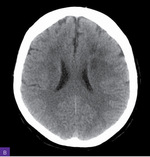

Rycina 2A, B. Rezonans magnetyczny głowy. Widoczne rozsiane ogniska i nieco większe obszary niedokrwienne w fazie ostrej z zakresu unaczynienia gałęzi tętnicy lewej środkowej mózgu, a także rozsiane zmiany wcześniej przebytych ognisk niedokrwiennych z zakresu unaczynienia tętnicy prawej środkowej mózgu

Diagnostykę poszerzono o badanie rezonansu magnetycznego (MR) w protokole udarowym. W badaniu opisano rozsiane ogniska i nieco większe obszary niedokrwienne w fazie ostrej z zakresu unaczynienia gałęzi tętnicy lewej środkowej mózgu, a także rozsiane zmiany wcześniej przebytych ognisk niedokrwiennych z zakresu unaczynienia prawej tętnicy środkowej mózgu (ryc. 2).